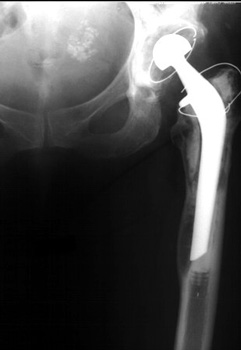

Cement fracture Gruen zone 6 close up next slide

CEMENT FRAGMENTATION

May occur with shift of femoral component.

Transverse fractures of cement near distal femoral stem seen in up to 1.5% of THR, associated with mild subsidence. If less than 4mm, usually not associated with failure. (Weber and Charnley)

CEMENT FRACTURE